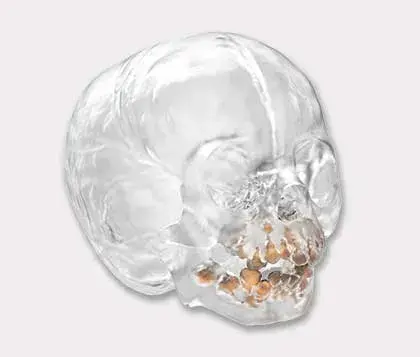

Models printed in flexible, rigid, opaque and clear materials

Translucent and opaque models printed in our high-strength materials*